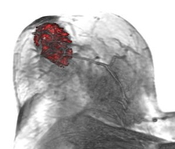

Breast cancer is the second leading cause of cancer deaths in women today. Although X-ray mammography is regarded as the most widely used method for early detection of breast cancer, the use of Contrast Enhanced MRI (CE-MRI) has gained considerable attention in the past years. Especially, Dynamic CE-MRI (DCE-MRI) considerably improves tumor classification by analyzing the flow of contrast agent within the breast tissue. In this paper we present MammoExplorer, an advanced CAD application that combines advanced interaction, segmentation and visualization techniques to explore Breast DCE-MRI data. In addition, we present a novel graphical representation of DCE-MRI data, new segmentation approaches, and a new way to explore temporal data.Additional Files and Images